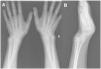

The wrist radiograph (Fig. 1) showed what seemed like a deviation of the distal epiphysis of the radius and a V-shaped carpus, with no differences between the two wrists. A watchful waiting approach was taken, with provision of conservative treatment with an elastic brace and analgesics and follow-up in the outpatient trauma clinic once Madelung deformity was confirmed with a CT scan (Fig. 2).

Madelung deformity is a rare congenital anomaly of the wrist involving a radial deformity with inclination of the radial physis toward the ulnar physis due to an abnormal Vikers ligament or asymmetric growth at the physis. It is more frequent in de girls with bilateral involvement and onset between ages 8 and 12 years.1 The diagnosis is made by means of plain radiography, which allows visualization of an increased distal radius volar tilt, subluxation of the ulnar head and a V-shaped carpus,2 although computed tomography or magnetic resonance imaging can be used to obtain higher-resolution images. The treatment depends on the level of pain and functional impairment, and conservative treatment with wrist splinting is usually sufficient.1